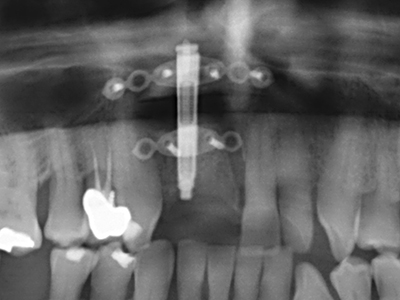

Пиезохирургията има допълнителни предимства при събиране на костни блокове. В допълнение към високата прецизност при остеотомията, описана по-горе, употребата на фините режещи накрайници значително намаляват загубата на материал. Голяма загуба на материал по време на събиране може да се очаква с дебелите накрайници, особено при употреба на борери Линдеман (Lakshmiganthan, Gokulanathan et al. 2012). Базалното разделяне, което е необходимо, особено за присадка на блок при ретромолар, е улеснено от специално създадени правоъгълни триони. В резултат на това, пиезохирургията е разглеждана като прецизна, улеснена и безопасна процедура за събиране на костни блокове в ретромоларното пространство (Happe 2007) (Фиг. 1-12).